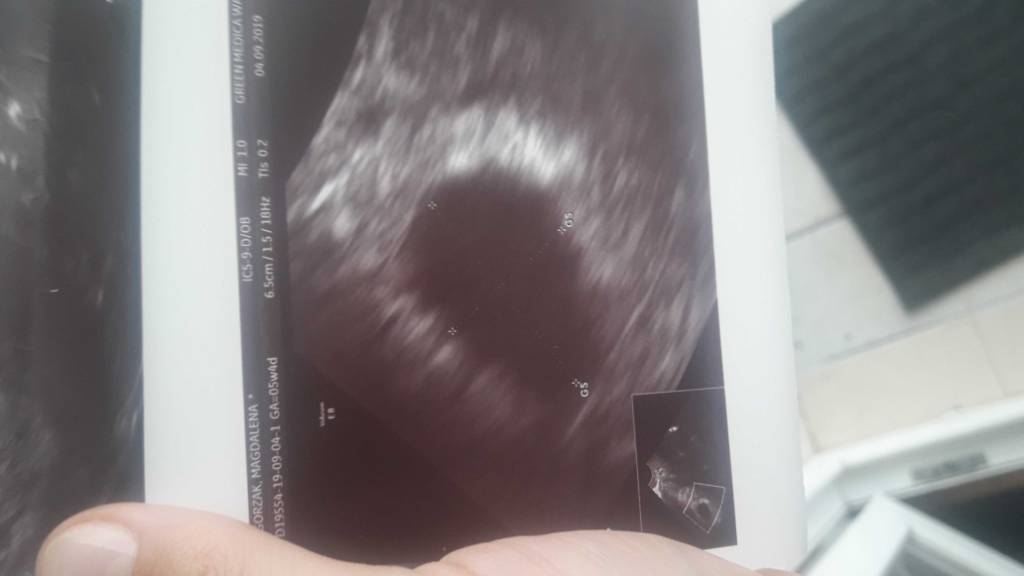

Szczerze mówiąc nie zapisywalam sobie nigdy w kalendarzu kiedy dostaje miesiączkę Ale każdego miesiąca pojawiała się między 15 a 20 więc wydaje mi się że jest w miarę regularnie 23.09 idę na wizytę wtedy dowiem się więcej bo może jest tak jak lekarz wyliczył z ostatnich pomiarów w piątek 6+3/4 Tylko pęcherzyk żółtkowy się schował i dopiero wczoraj mógł to lekarz znaleźć! A moje wnioski są spowodowane tym iż mniej-więcej około 6 sierpnia zaczęły mnie boleć piersi jak przed miesiączka I wiedziałam że coś jest nie tak bo za wcześnie na miesiączkę Ale test zrobiłam dopiero 20-tego jeden rano drugi popołudniu i oba były pozytywne a na jednym z nich pokazało 2-3 tygodnie

Witajcie. Moja sytuacja jest taka, że na usg 5tyg+4 dni nie było zarodka, ciałko żółte słabo widoczne. Pani doktor poleciła zrobienie beta hcg i 06.09 było 23 696 a 09.09 36 647, bardzo się stresuję bo to zdaniem lekarki za mały przyrost. Wizyta dopiero 16.09. Czy któraś z Was miała podobnie z przyrostem bety?

Ja nie wie jak jest u mnie z beta bo nie robiłam ale ostatnie 3 tyg to koszmar stres itd. Poczytaj wczesniejsze posty . U mnie w 5+4 byl tylko pusty pecharzyk ciazowy dopiero wczoraj lekarz znalazl pęcherzyk żółtkowy + krwawienie nie duze . A twraz ide dopiero za 2 tygodnie i nadal sie stresuje chociaz troche mniej bo nadal nie widziałam ani fasoli ani serduszka więc jedyne co nas uratuje to cierpliwość . Życzę wytrwałości i dużo zdrówka